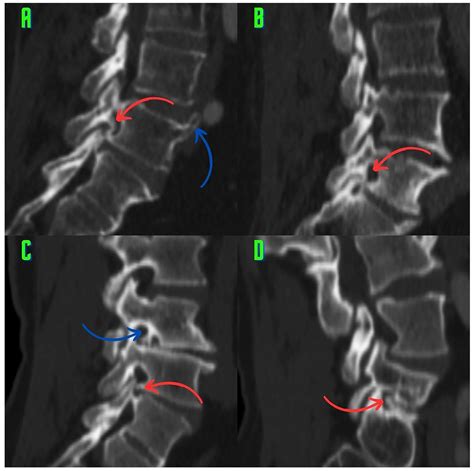

• Imaging Studies: Various imaging techniques are used to visualize the spine and identify the presence of osteophytes. These may include:

CT Scans Offer detailed images of the bony structures and can help identify the location and size of osteophytes.